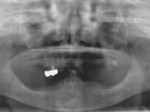

片側2歯欠損片側2歯欠損片側2歯欠損 主訴-入れ歯を使ってみたが違和感強くてダメ。固定のものにしたい。術前下顎口腔内(鏡像) 二次オペ時(鏡像)二次オペ時(鏡像)二次オペ時(鏡像) 術後術後術後、左下奥2本インプラント(鏡像) 術後(レントゲン)術後(レントゲン)術後(レントゲン)、左下奥2本インプラント